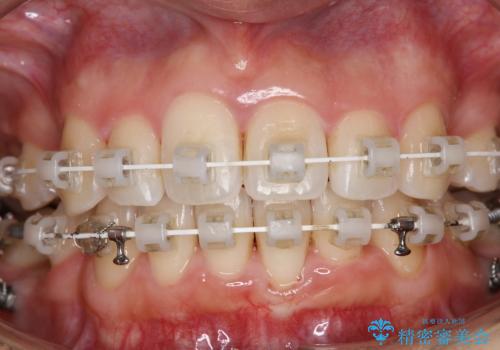

ワイヤー矯正治療中に歯の着色を綺麗に

- ワイヤー矯正治療中にクリーニングを希望されました。

日常的にコーヒーを飲むそうで、装置周りの着色が気になるとのことでした。

エアフロー60分コースを行いました。

ワイヤー矯正中はブラッシングが難しくなるため、磨き残しが多くなることがあります。

また、矯正で歯の移動があると今までなかったところに隙間が出てきたり、ガタつきが解消されてきたりすることで、お口の中の環境が変わります。

矯正治療中も清潔な口腔内を保つことは、とても大切です。そのため、定期的に専門的な機械・材料を使用したクリーニングを行うことがおススメです。